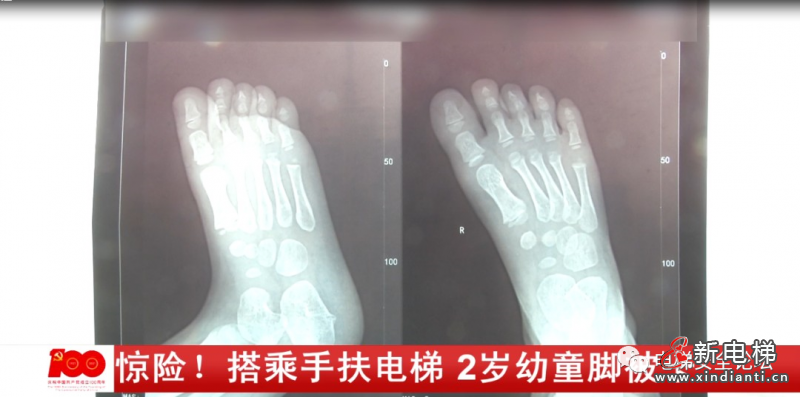

奶奶介紹,當(dāng)時情況十分危急,孩子的右腳被卡進(jìn)電梯的縫隙里,孩子不停的在哭喊,工作人員將孩子的腳解救出來時,腳已經(jīng)被卡得變形。小西的奶奶:那只腳小腳趾還好一點,其他的腳趾尤其是大腳趾都被卡得白白的扁扁的,我以為我小孩的腳殘廢了,沒用了。事后,小西被緊急送往附近的醫(yī)院進(jìn)行治療,幸運的是孩子受傷的腳并沒有骨折。